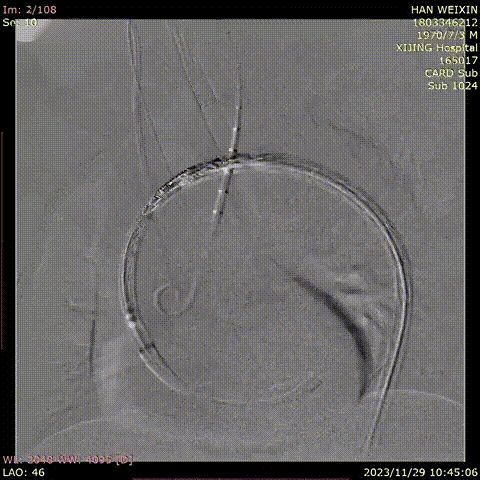

韩某,男,53岁,“查体发现主动脉弓部溃疡15天”入院,主动脉CTA提示:主动脉溃疡(弓部);2. 主动脉壁内血肿。患者高血压病史8年,最高210/130mmHg,无规律服药。

术前 CTA

术前造影

导入弓部

主体支架

释放弓部

超选左颈总动脉

超选无名动脉

并预置导丝

导入左颈总

支架并释放

导入无名动脉

超选左锁骨下

动脉

导入左锁骨下动脉

导入并释放远端支架

术前

术后

手术用时115分钟